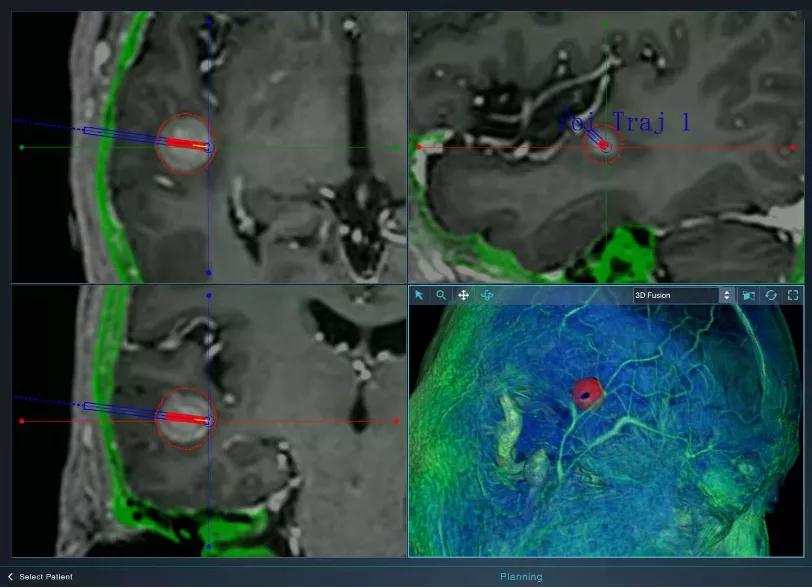

经过手术团队和华科精准工程技术团队共同评估,手术在北京天坛医院核磁手术室进行。精准定位是微创颅内消融的第一步,手术首先利用华科精准手术机器人系统精准地避开颅内血管将消融光纤植入预定位置和路径。在贾旺教授的指导下,手术共实施3次消融,共1150秒,消融病灶3020.93立方毫米。

脑转移瘤术中LITT实施

利用手术机器人进行消融光纤精准定位突破了传统神经外科手术机器人只能做手术辅助定位的局限,使得手术机器人可以全面覆盖从诊断到手术治疗的整个环节。术后头颅CT显示患者无明显出血、水肿,患者术后次日即正常下床活动,目前已顺利出院。